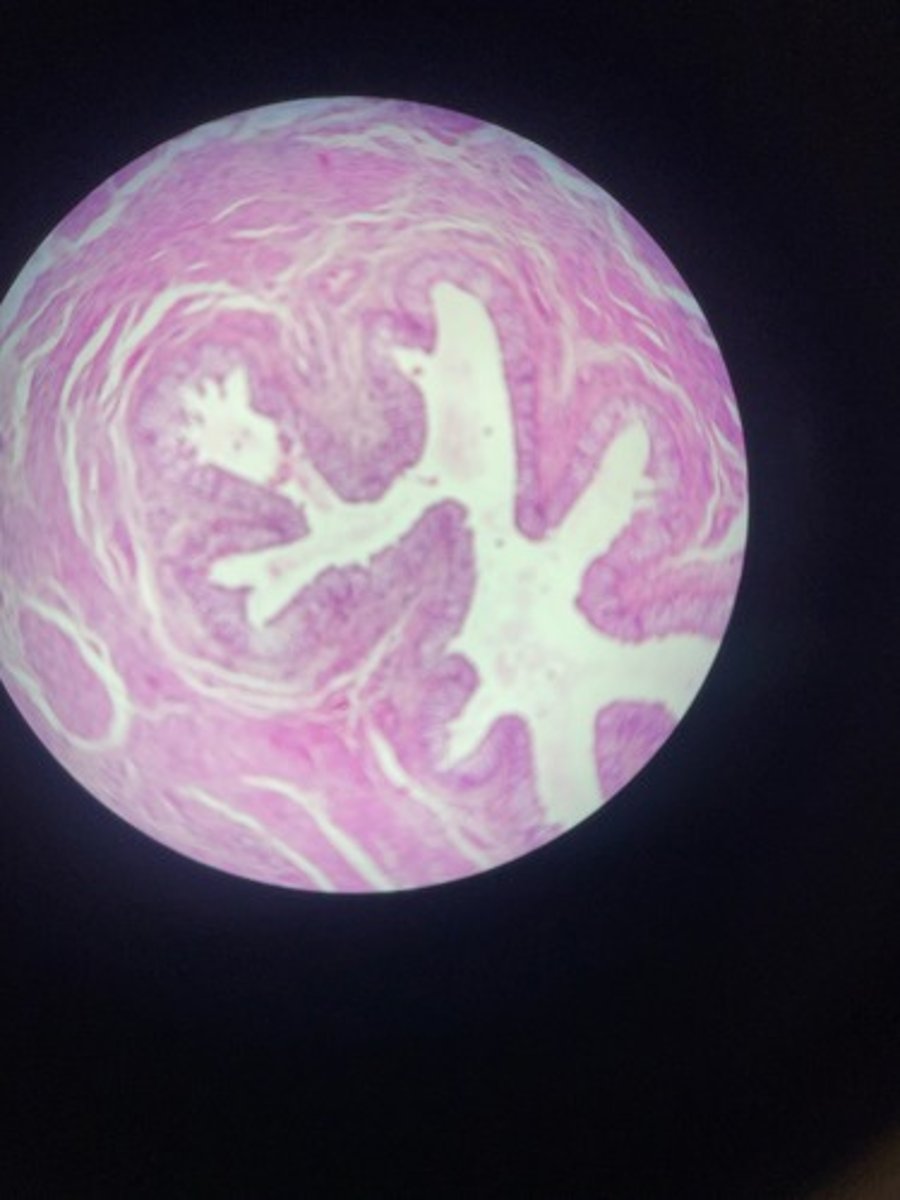

Prostate HE

Prostate HE

Prostate HE

Prostate HE